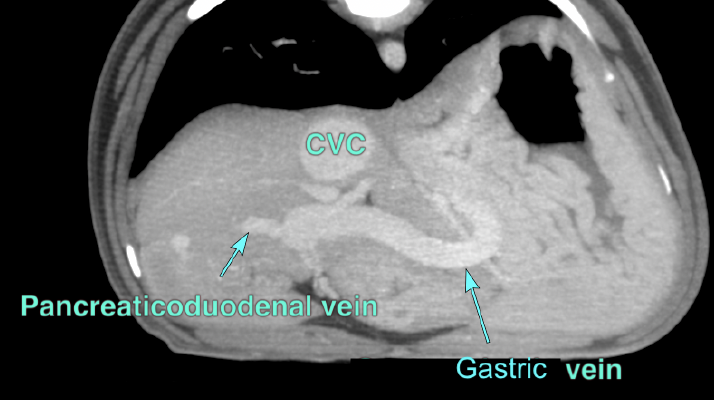

A computed tomography (CT) scan was subsequently performed, which confirmed the presence and specific location of the shunt, providing valuable information for guiding the next steps in the pet’s surgical plan.

INTERPRETATION OF THE CT FINDINGS:

- Single extrahepatic portosystemic shunt, connecting from the right gastric vein via the left gastric vein, which receives the splenic vein, to the caudal vena cava.

- An additional abnormal connection of the left pancreatic vein to the portal vein appears to be present in the region of the expected entrance location of the splenic vein.

- Associated mild microhepatia.

The Gastroduodenal vein (GDV) and splenic vein normally empty into the portal vein (PV) separately like the above image.

In this patient, the gastroduodenal vein receives the splenic vein, is enlarged and empties abnormally into the caudal vena cava.